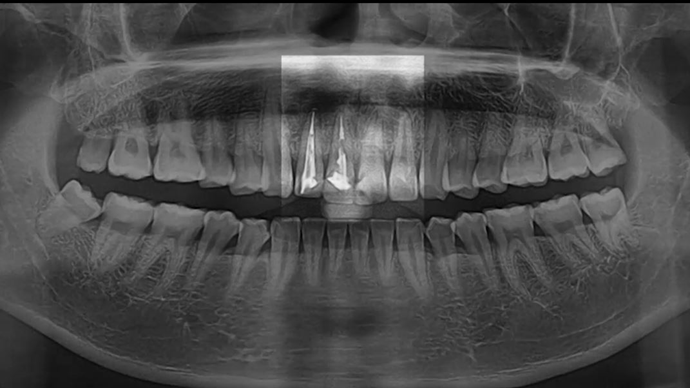

Clinical case: Extraction, immediate placement & loading using

R2GATE solution in aesthetic zone

- Courtesy of Dr. Jong-Cheol Kim, Korea-